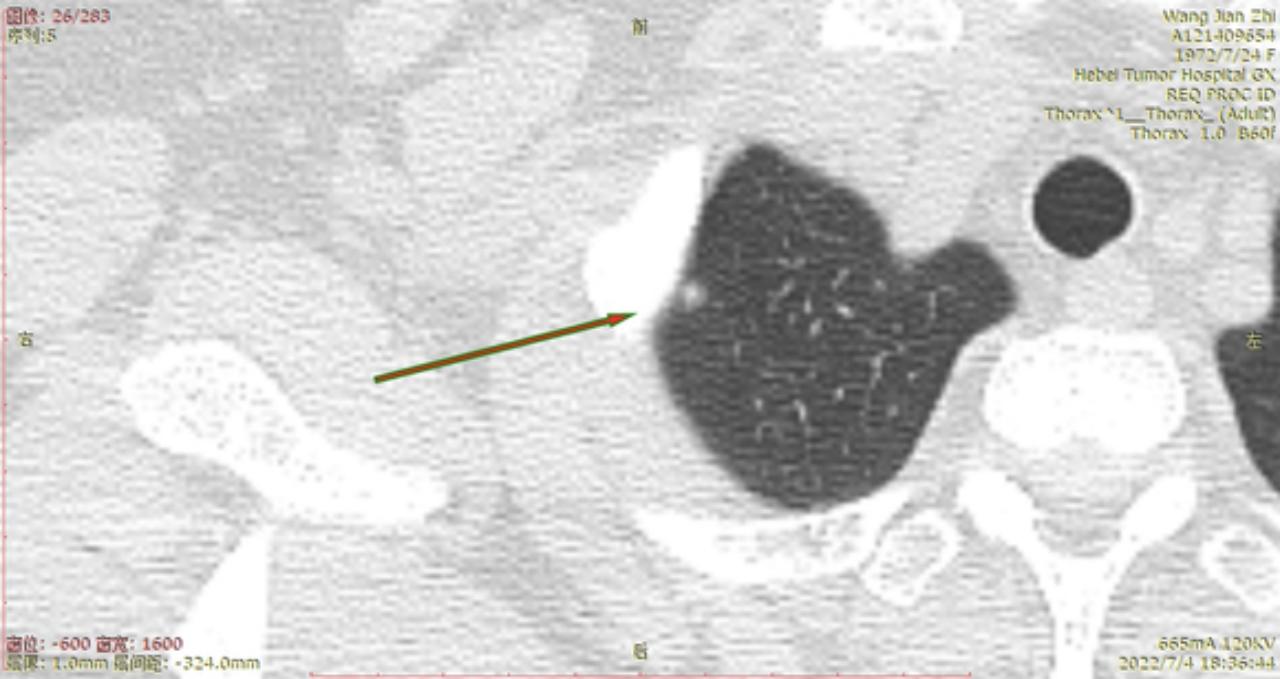

结1

结2

结3

右侧至少5枚以上的微浸润或原位腺癌,大的两枚结节微浸润,建议半年内把右侧5mm以上或者有危险的结节一网打尽。左侧结节还安全,安心随访